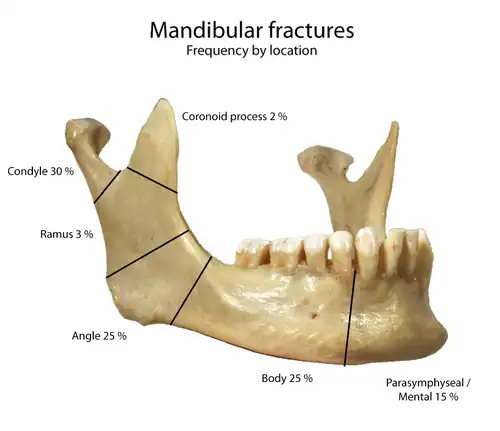

Classification

There are various classification systems of mandibular fractures in use.

Location

This is the most useful classification, because both the signs and symptoms, and also the treatment are dependent upon the location of the fracture.[6] The mandible is usually divided into the following zones for the purpose of describing the location of a fracture (see diagram): condylar, coronoid process, ramus, angle of mandible, body (molar and premolar areas), parasymphysis and symphysis.[6]

Mandibular fractures are typically the result of trauma.[1] This can include a fall onto the chin or a hit from the side.[1] Rarely they may be due to osteonecrosis or tumors in the bone.[1] The most common area of fracture is at the condyle (36%), body (21%), angle (20%) and symphysis (14%).[1] Rarely the fracture may occur at the ramus (3%) or coronoid process (2%). While a diagnosis can occasionally be made with plain X-ray, modern CT scans are more accurate.[1]